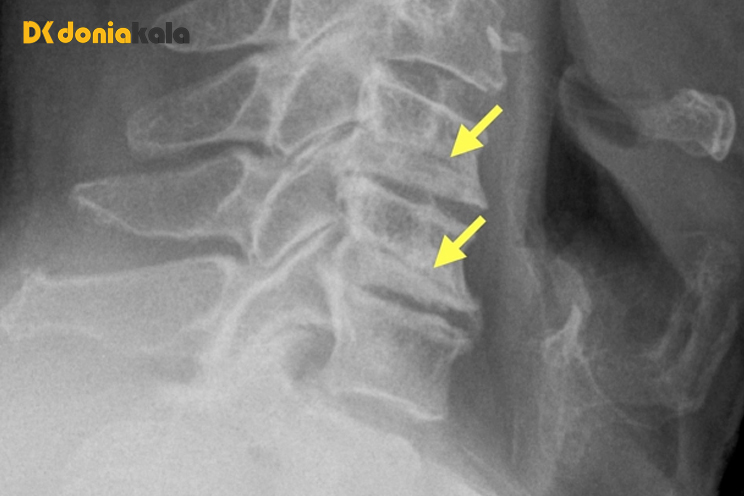

تشخیص آرتروز فاست Facet joint arthrosis:

تشخیص علت کمردرد ممکن است دشوار باشد. برخی از آزمایشات تصویربرداری مانند تشدید تصویر مغناطیسی (MRI)، اشعه ایکس، و اسکن توموگرافی کامپیوتری (CT) میتوانند به ارائهدهنده مراقبتهای بهداشتی شما کمک کنند تا ببیند آیا آرتروز آسیب قابل مشاهدهای به مفاصل فاست و بافت اطراف شما وارد کرده است یا خیر.